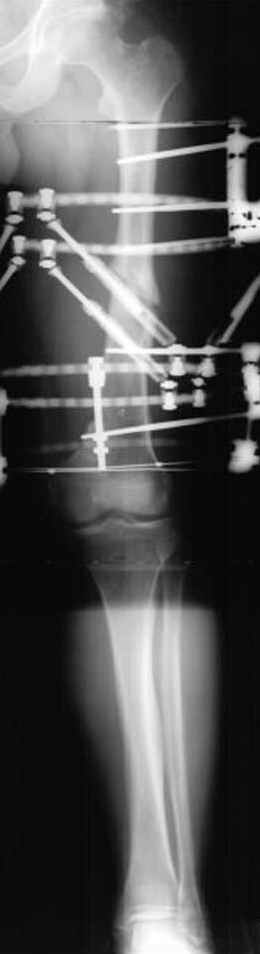

Несколько снимков из моей коллекции, чтобы разьяснить, почему мы до сих пор делаем различные варианты остеотомии.

Djoldas Kuldjanov 23 Ноябрь 2004, 18:21

пластическая модель; и коррекция бедра аппаратом Илизарова.

хотя даже если бы и инфекция , то nail exchange с рассверливанием канала - вариант дебрайдмента) Я думаю, что последовательность развития событий:

Узкий к-м канал - тонкий гвоздь- усталостный перелом дистальных винтов - развитие нестабильности и как ее результат остеолиз вокруг гвоздя - деформация анатомической оси бедра. Похоже, что я понял почему аппарат, а не новый гвоздь:-)